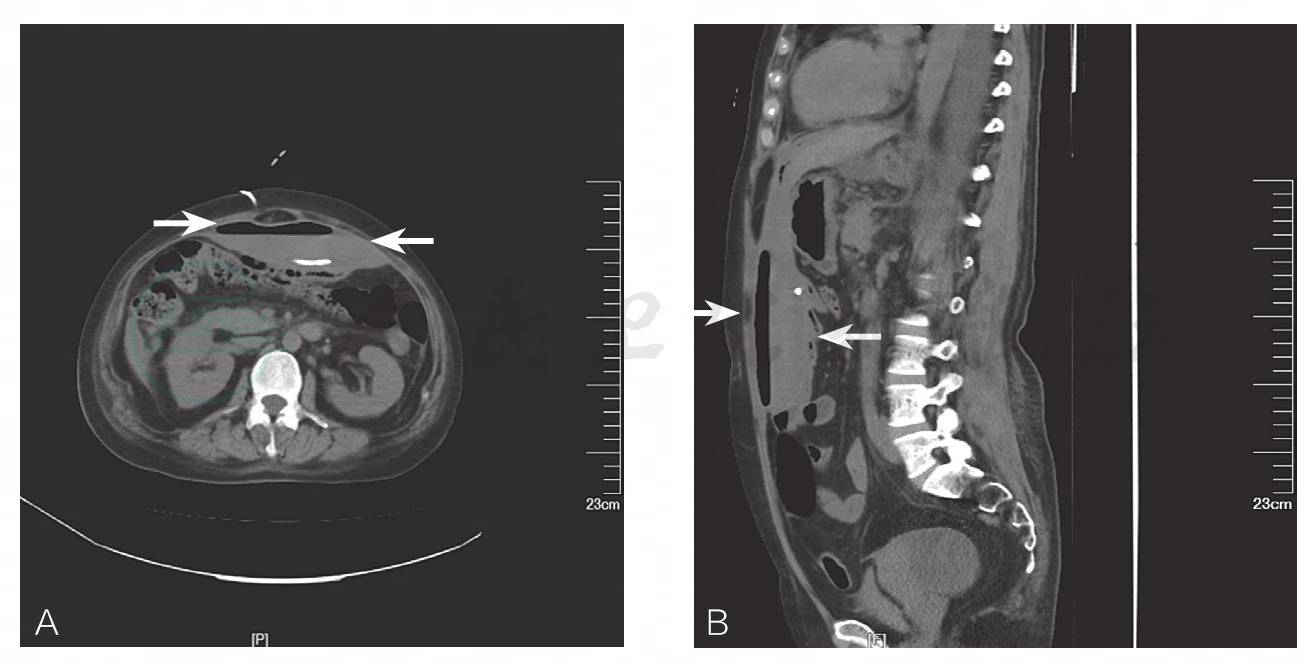

腹部立卧位平片及全腹CT:双侧胸腔积液,右肺下叶炎性实变;腹腔前壁巨大包裹性积气积液,其内可见气-液平面,部分肠管积气(图1、图2)。

腹腔前壁巨大包裹性积气积液,其内可见气-液平面

腹腔前壁巨大包裹性积气积液,其内可见气-液平面,部分肠管积气